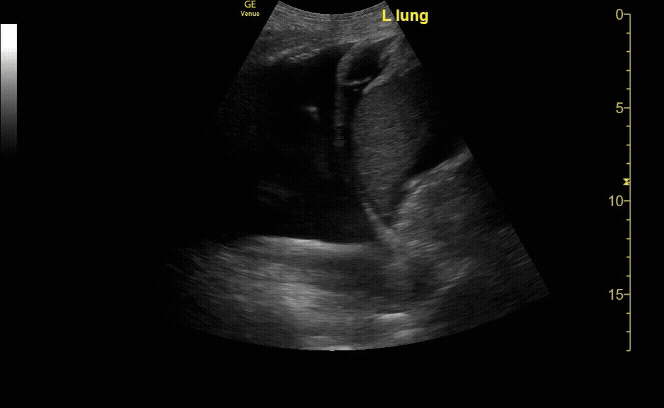

RUQ View with window curtain sign.

c/o Vishal Mittal, MD